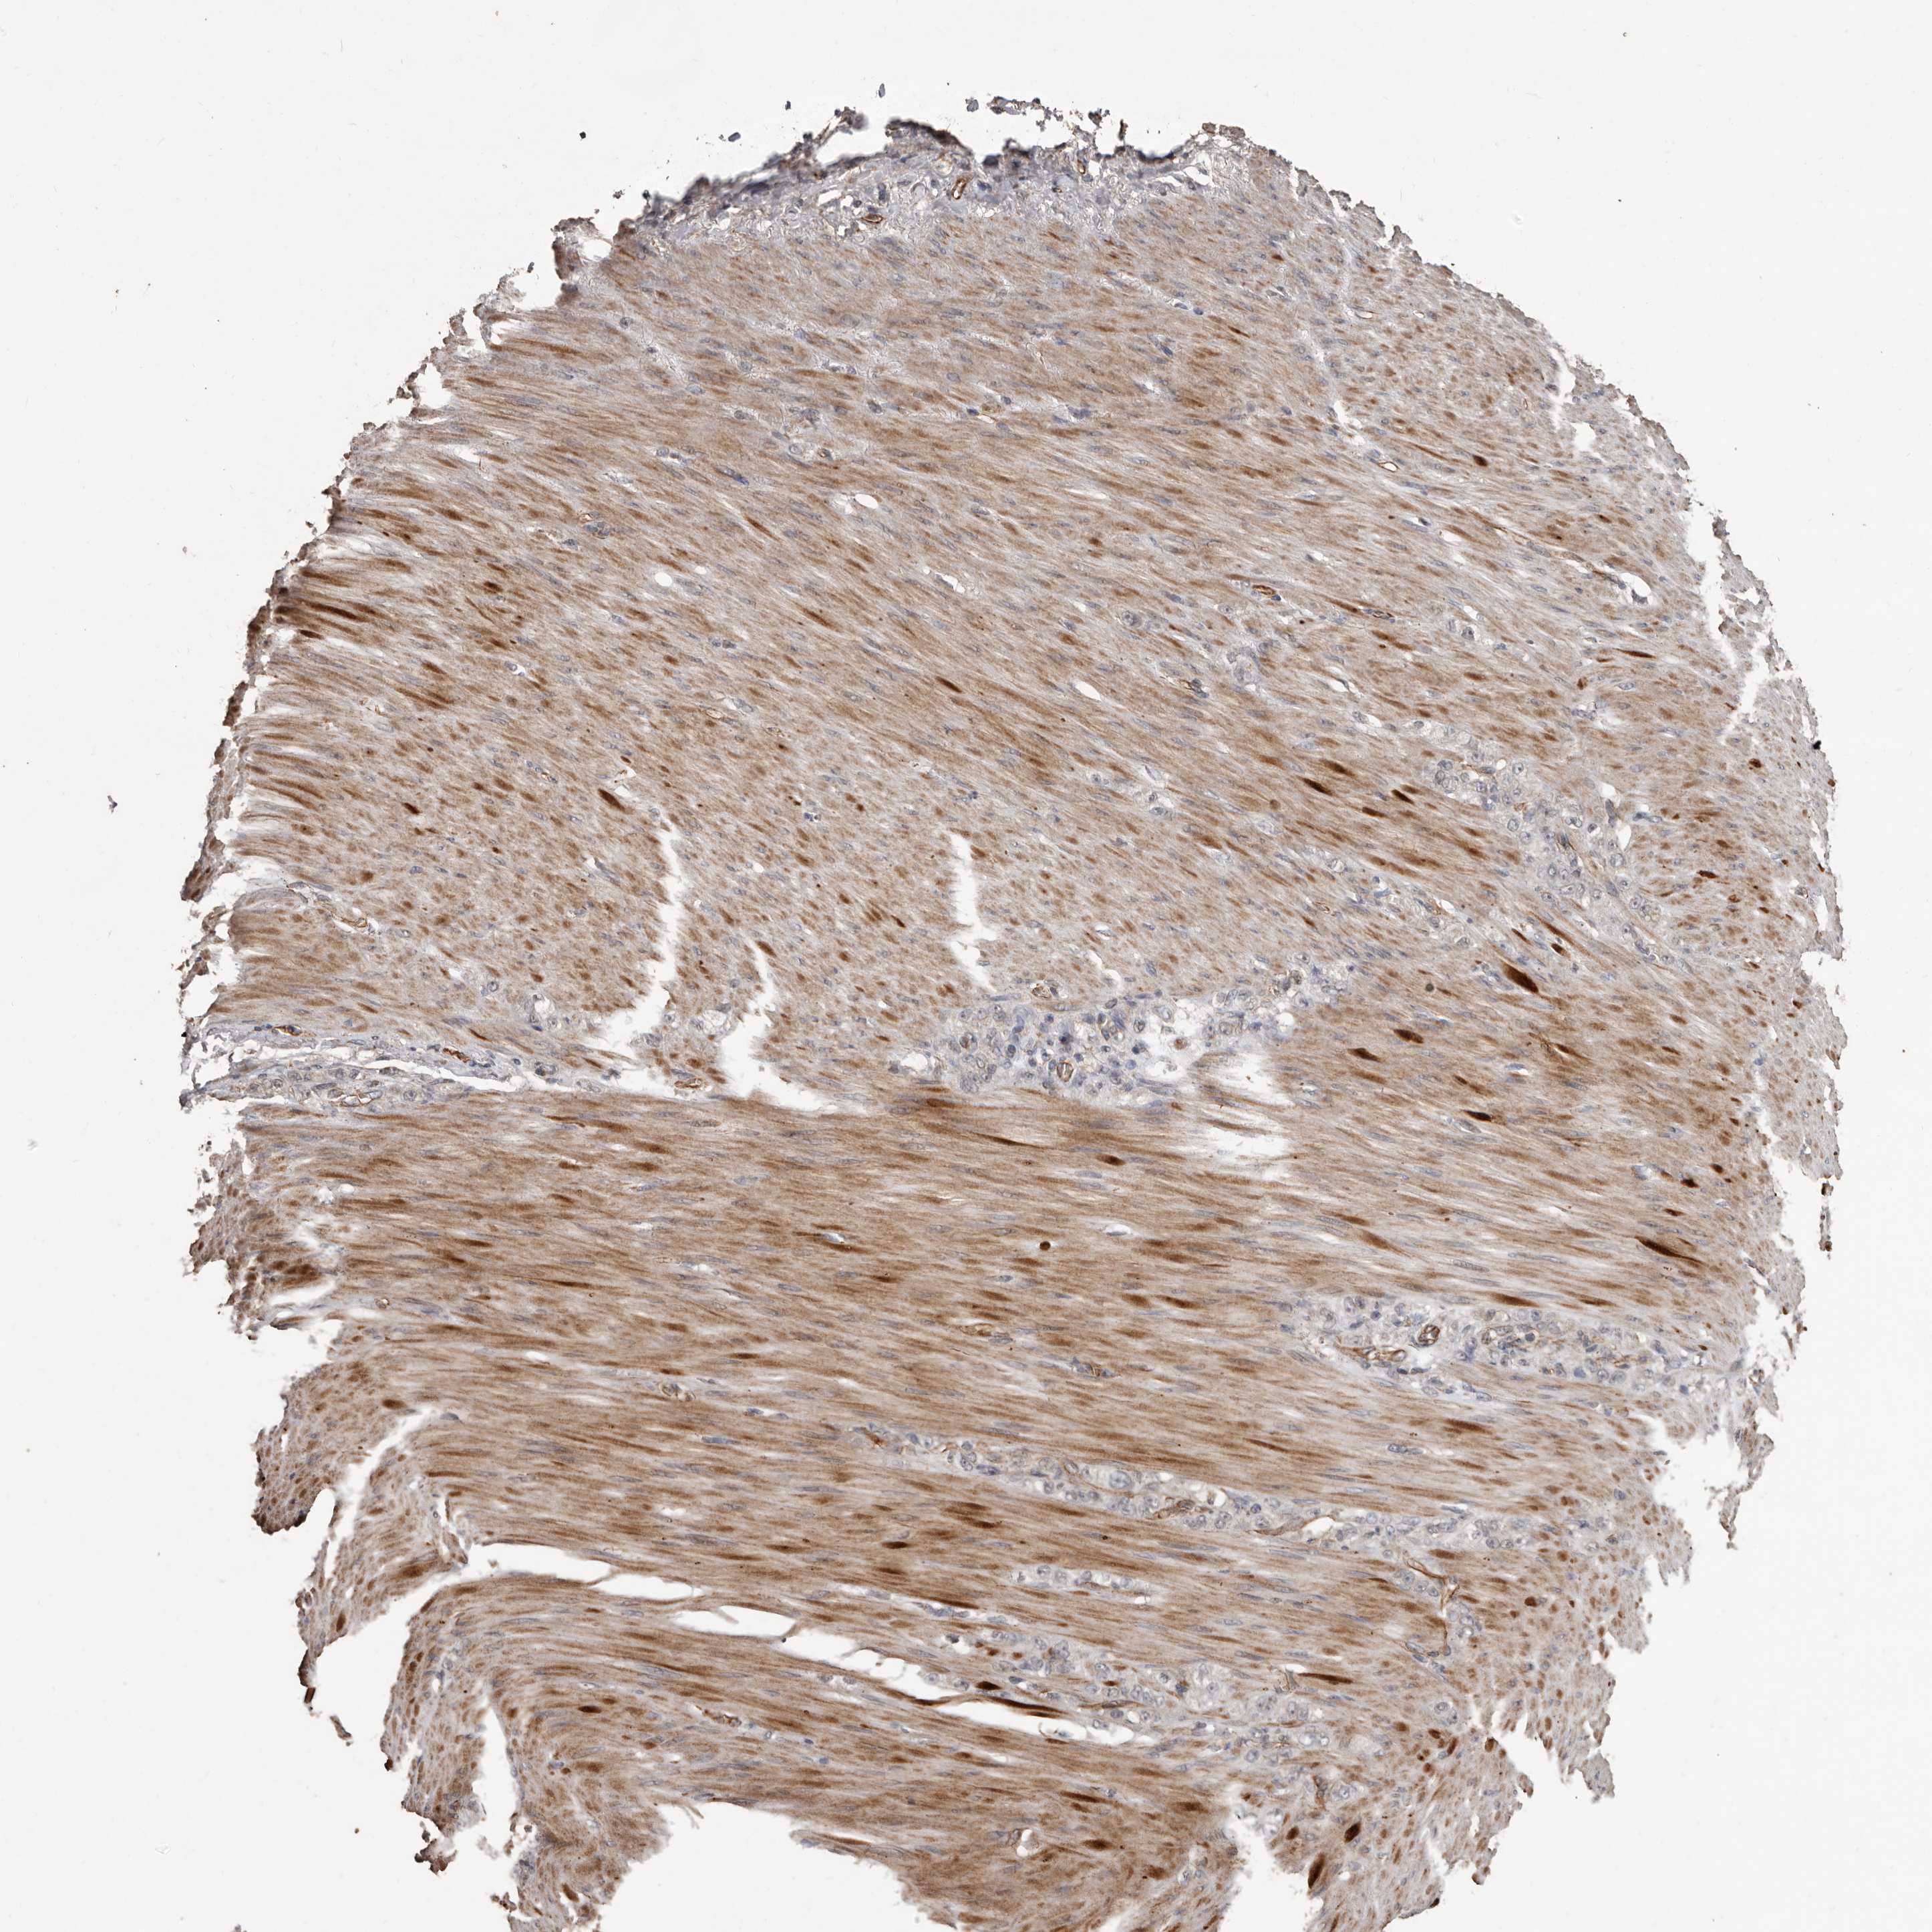

STOMACH CANCER - Protein expressioni

A mouse-over function shows sample information and annotation data. Click on an image to view it in a full screen mode. Samples can be filtered based on level of antibody staining by selecting one or several of the following categories: high, medium, low and not detected. The assay and annotation is described here.

Note that samples used for immunohistochemistry by the Human Protein Atlas do not correspond to samples in the TCGA dataset.

Antibody stainingi

Antibody staining in the annotated cell types in the current human tissue is reported as not detected, low, medium, or high, based on conventional immunohistochemistry profiling in selected tissues. This score is based on the combination of the staining intensity and fraction of stained cells.

Each image is clickable and will lead to virtual microscopy that enables deeper exploration of all samples and also displays staining intensity scores, fraction scores and subcellular localization as well as patient and tissue information for each sample.

Antibody HPA029455

Staining

High

Medium

Low

Not detected

Intensity

Strong

Moderate

Weak

Negative

Quantity

>75%

75%-25%

<25%

None

Location

Nuclear

Cytoplasmic/membranous

Cytoplasmic/membranous,nuclear

Adenocarcinoma, NOS